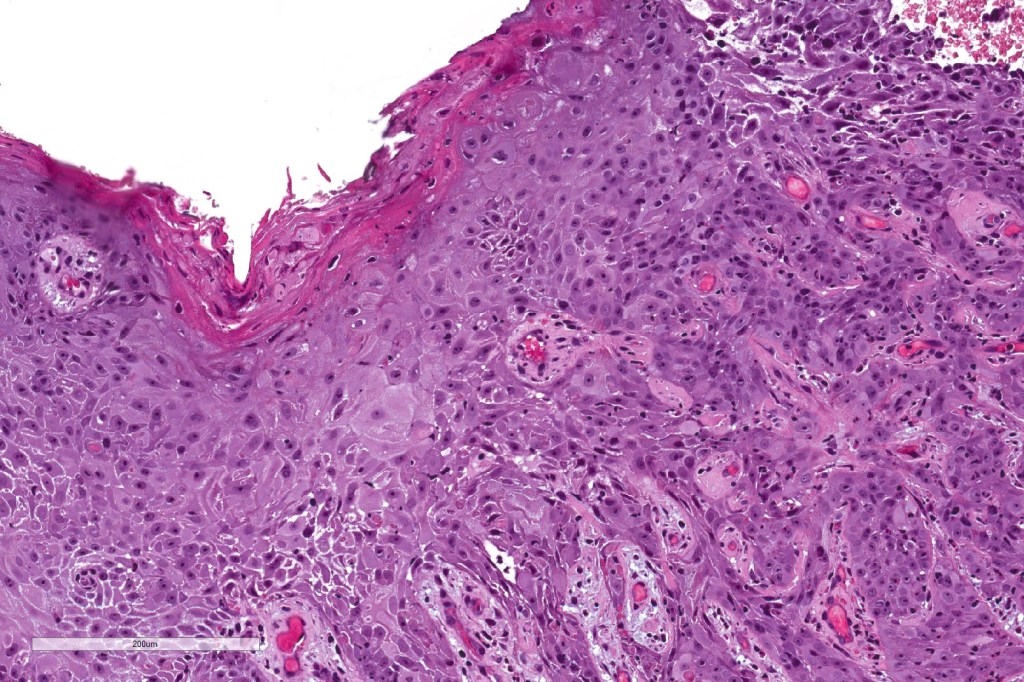

Histological features

•In situ (malignant hidroacanthoma simplex)

•Continuity/origin from epidermis (arises from the acrosyringium, distinguishes this tumor from hidradenocarcinoma)

•Pushing or infiltrating deep margin

•Squamous differentiation